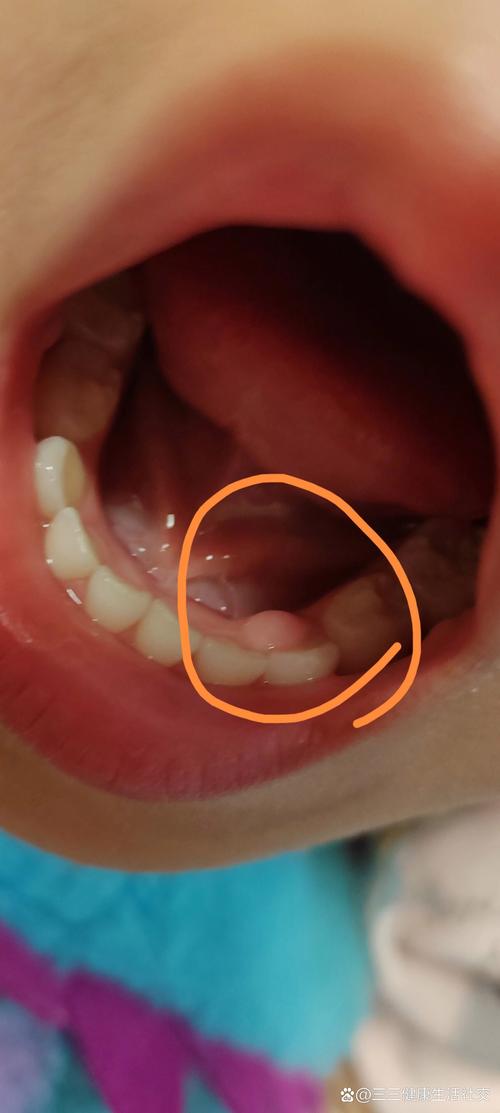

萌出性牙龈囊肿 (Eruption Cyst) - 常见于长牙期

这是乳牙或恒牙快要萌出时,牙齿上方的牙龈组织内形成的充满液体或血液的囊肿。

- 特点:通常出现在即将长牙的牙龈位置,是一个蓝色或紫色的、半透明的小水疱或肉疙瘩,大小像一颗小豌豆,它通常不疼,随着牙齿萌出会自行破裂消失。

- 诱因:正常长牙过程中的生理现象。